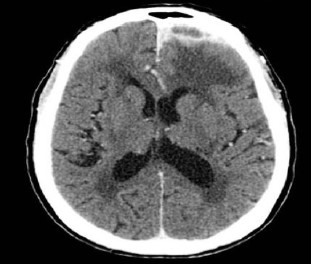

Diagnosticado com HIV/AIDS, neurotuberculose e tuberculose pulmonar miliar. Seguem exames de imagem.